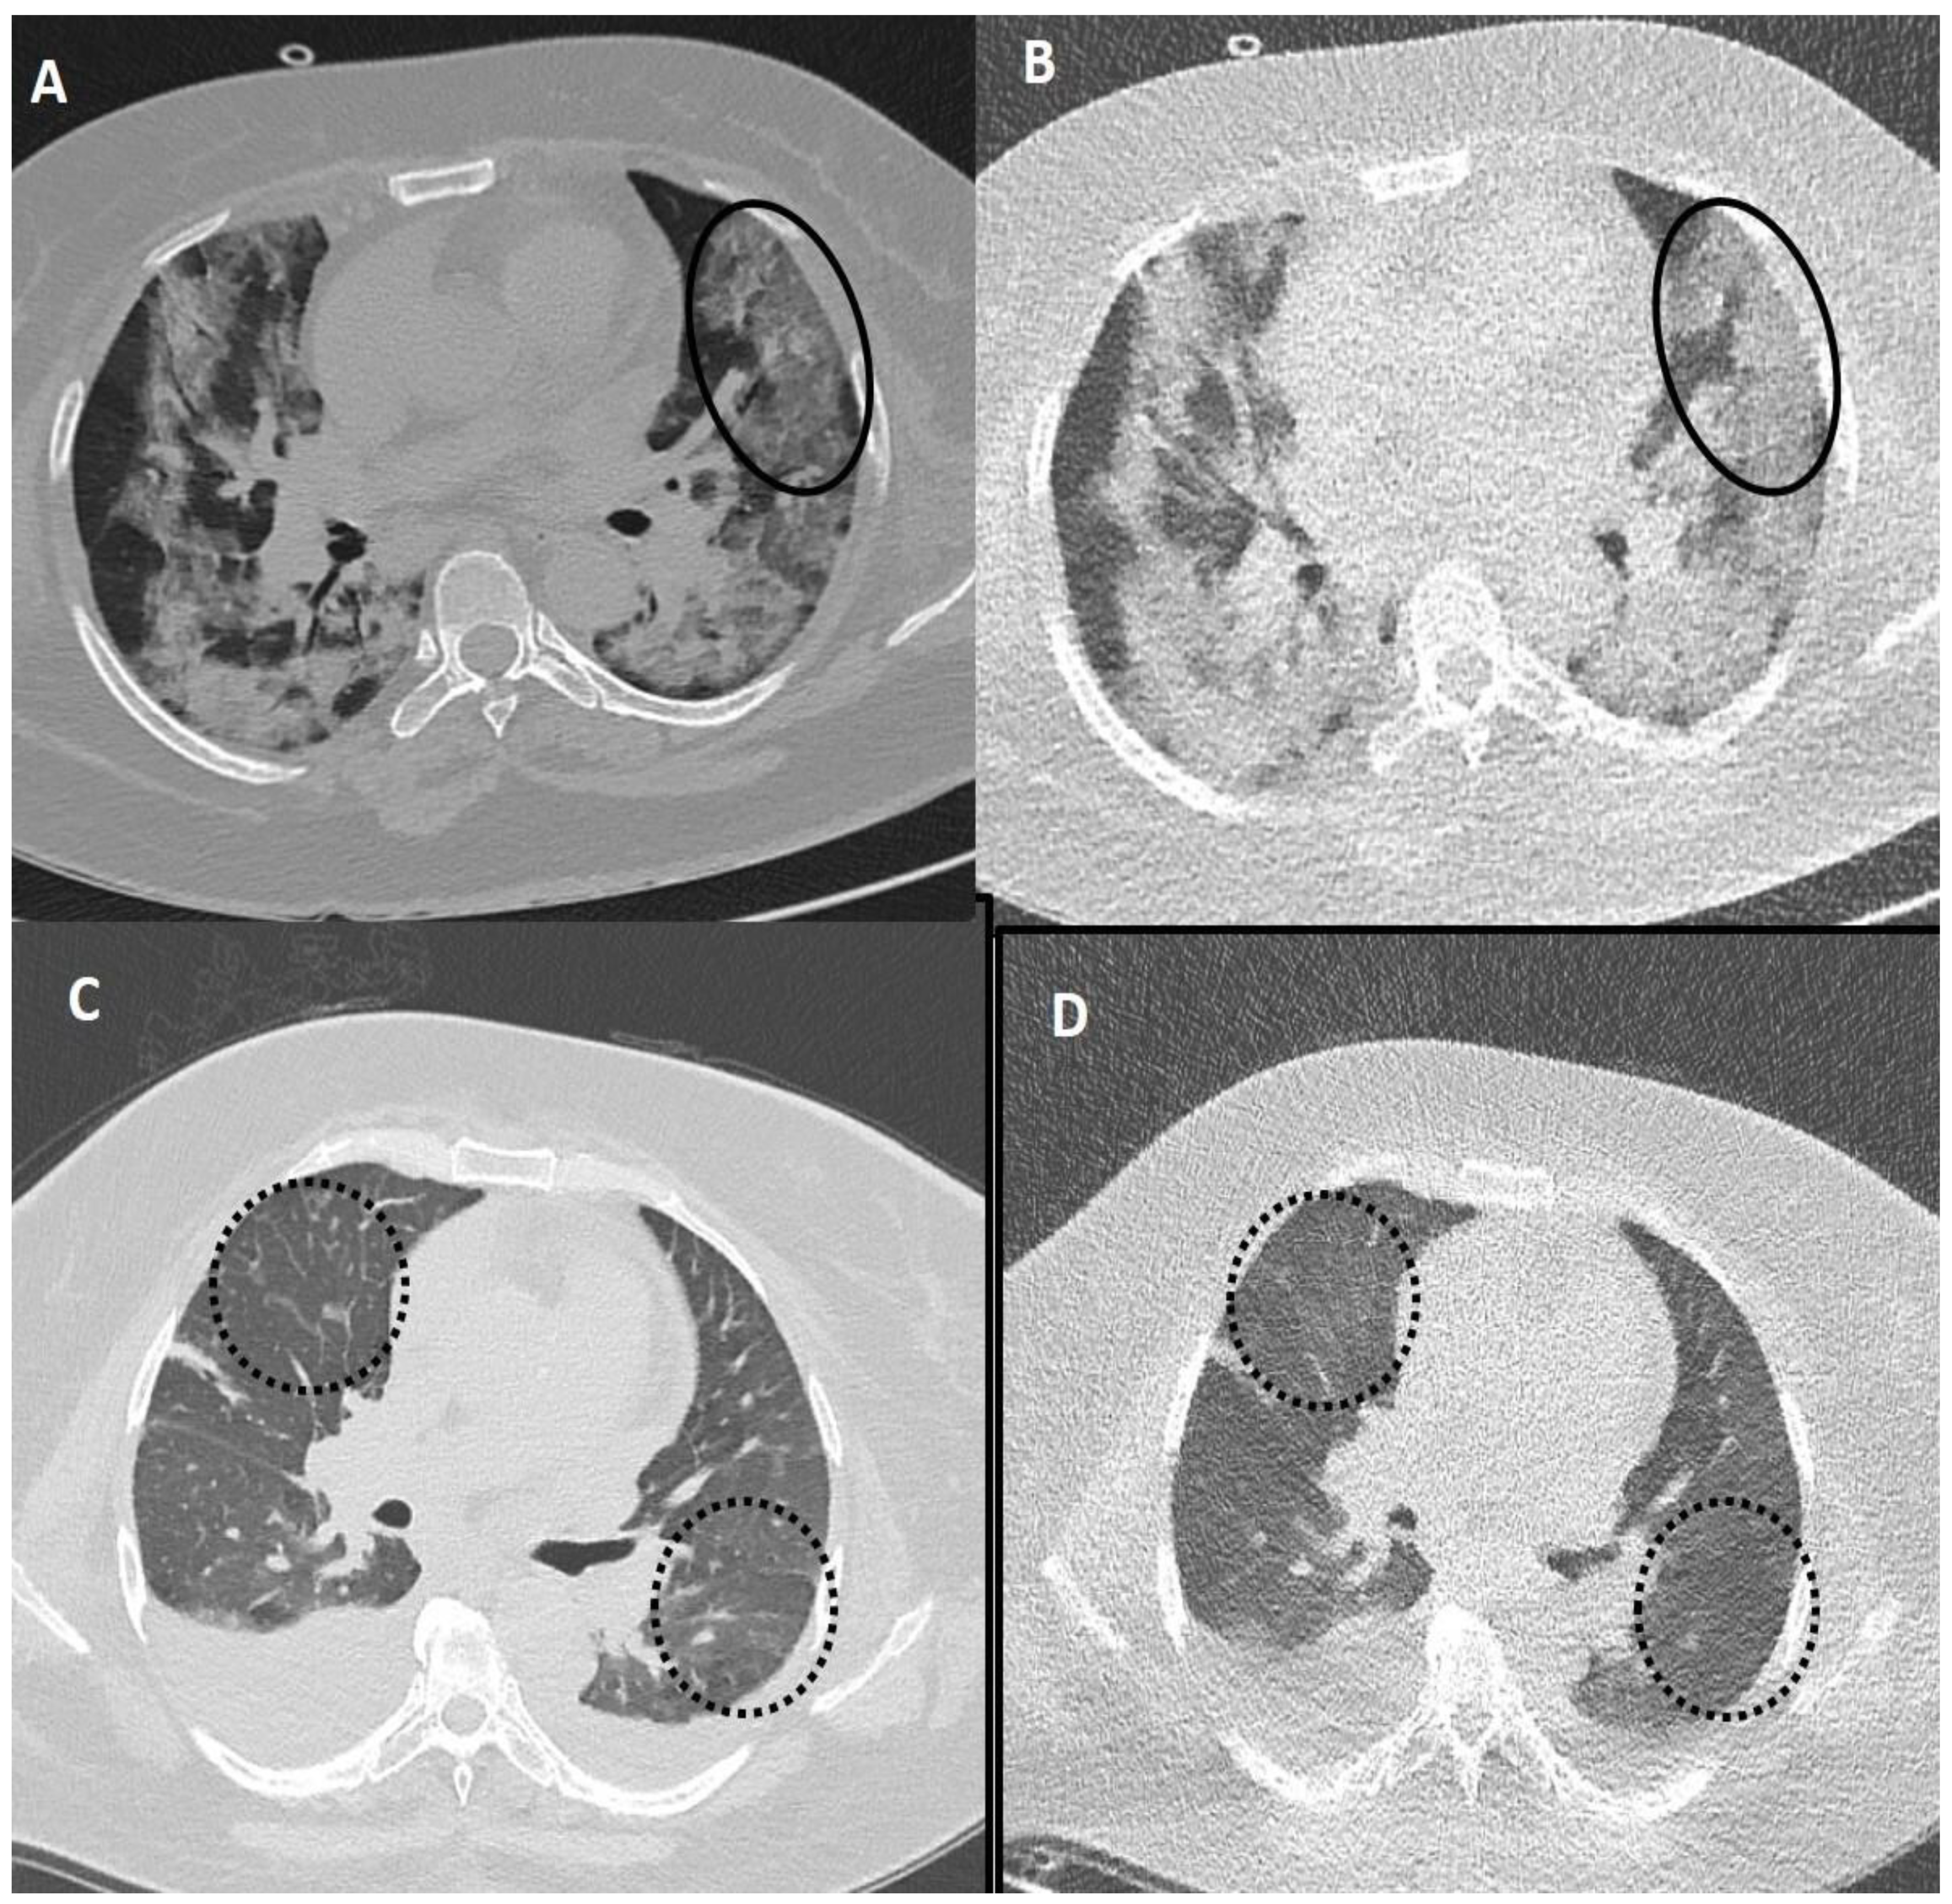

Figure 5.

Fallacies of ultra-low dose CT (ULDCT) chest in two different COVID-19 patients: (A,B) A 53-years old female patient with SDCT (A) showing areas of GGOs in the left lung (black circle) and in the corresponding ULDCT (B) these areas of GGO’s were misinterpreted as consolidation (black circle). (C,D) SDCT images in another patient (C) showing subtle interlobular septal thickening in bilateral lungs (dotted circles) that was missed on the corresponding ULDCT (D) images (dotted circles). CT severity score calculated on SDCT and ULDCT, however, was similar in both patients.